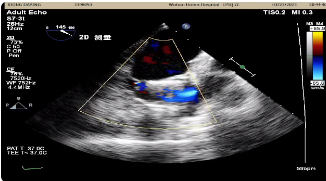

心超显示:主动脉瓣为三叶瓣,瓣尖增厚,回声增强,瓣叶开放未见明显受限,闭合不佳。瓣环内径约2.1cm,主动脉窦部内径约3.6cm,窦管交界处内径约3.4cm,升主动脉内径约4.4cm;左心增大,左房前后径3.9cm,横径约4.4cm,长径约6.3m;左室前后径约4.8cm,横径约4.5cm,长径约7.9cm。

彩色多普勒显示:主动脉瓣口舒张期左室流出道侧见中至大量反流信号,峰速2.4m/s,压差24mmHg,LVEF 64%。

超声诊断:主动脉瓣重度关闭不全;升主动脉明显增宽;左心增大。

即刻复查食道超声,瓣架深度合适,未见明显瓣周漏: